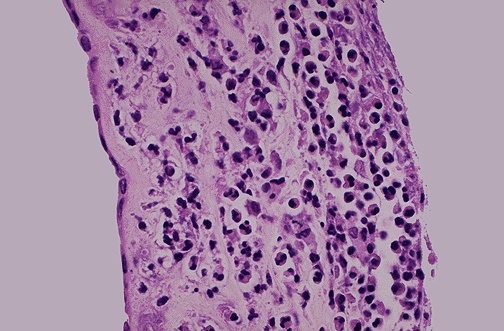

Image 4.2

The fetal membranes and cord are shown here. What is wrong?